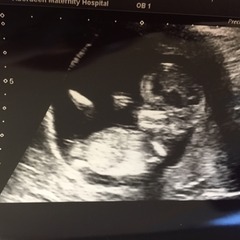

Jw35 · 25/01/2016 13:15

SmileSmileSmileSmileSmileSmileSmileSmileSmileSmileSmileSmile

Today is the best day of my life! New due date July 30th!! I'm 13+2! Woohoo! So happy! Baby wa wriggling about! Yay!

Brilliant pics Jw, we are due date buddies! I'm glad you had a good scan.

Congrats JW!! How very cute. Your DD looks so proud!

Sorry JW, must have missed the last page of posts. Great pics!! So happy for you Grin

jw what gorgeous pics of your perfect looking baby! love the one of your little girl too, so excited!

Jw hi baby! Great pics, your DD is super cute and looks like she's going to be a good big sis! So glad all went well.